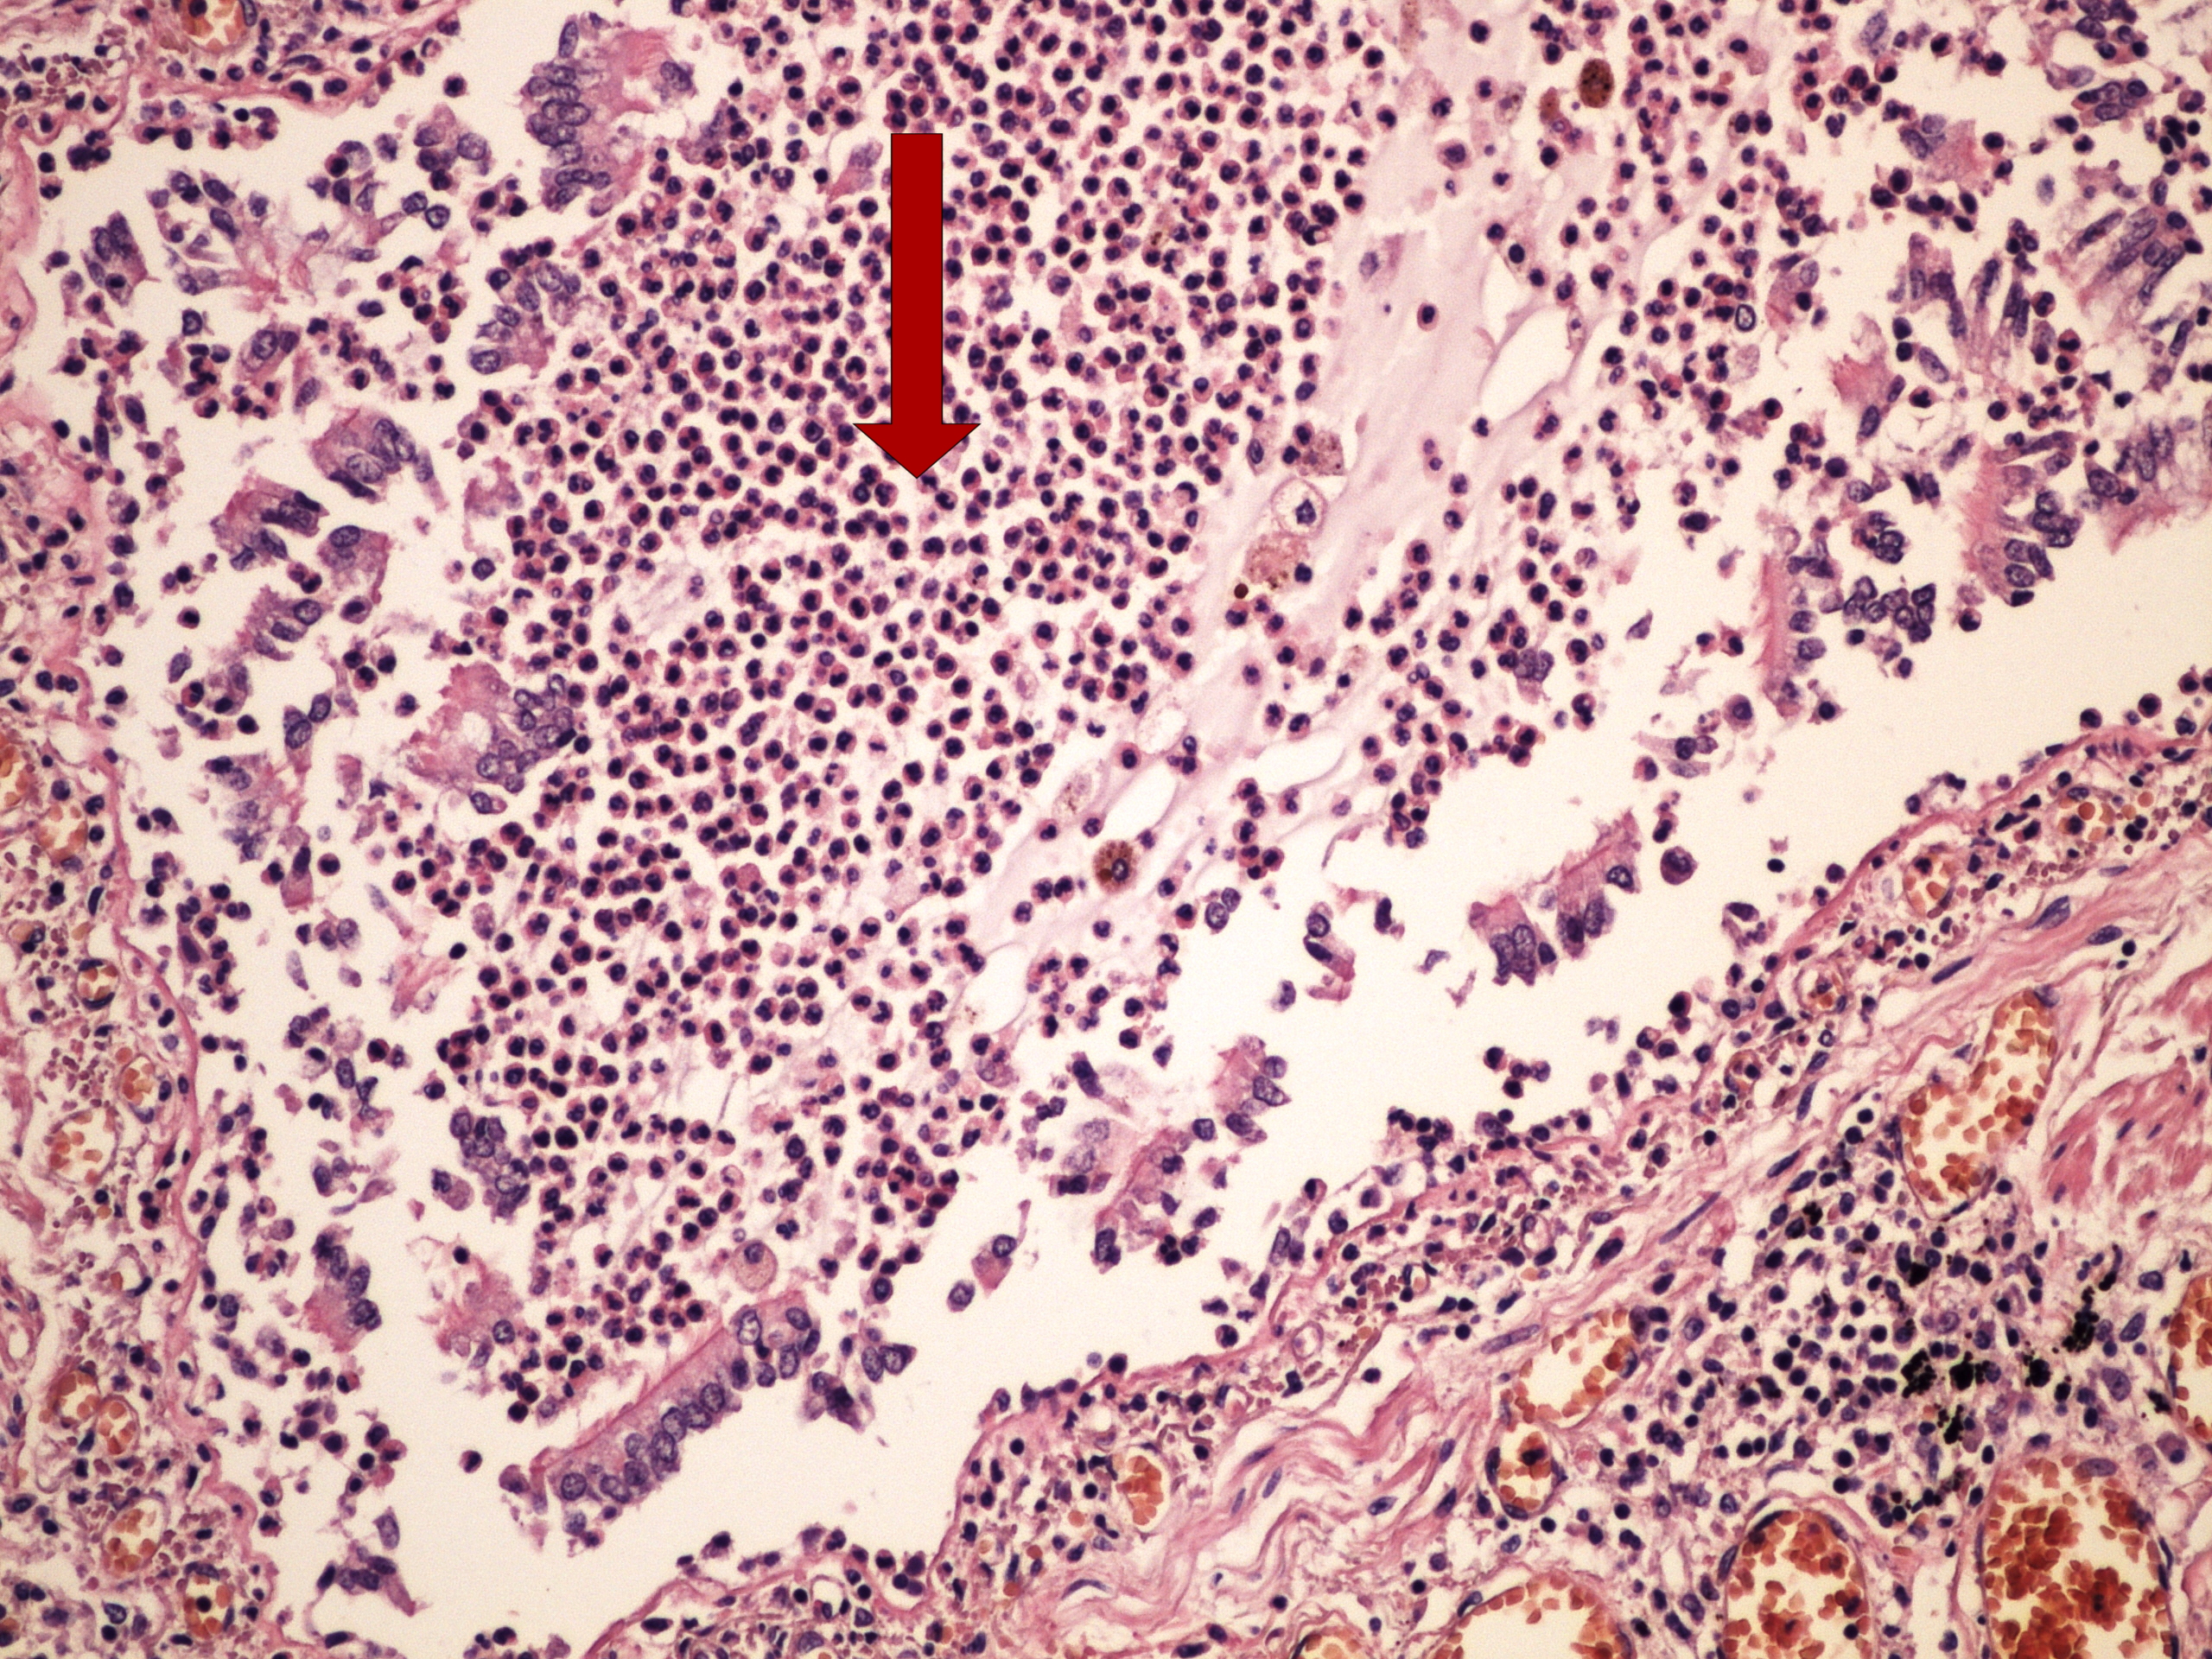

Preparát č.9 a č.10 - chronický plicní absces

Struktury

- nespecifická granulační tkáň